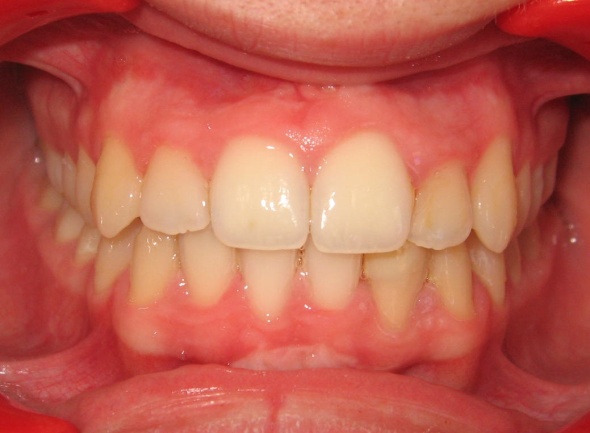

Ce cas illustre parfaitement que l’orthodontie ne peut pas se résumer à un simple alignement des dents. Ici, l’exclusion de la canine supérieure gauche (23) pouvait faire croire à un manque de place dû à un excès de volume dentaire. En réalité, un diagnostic précis a révélé deux causes : une endomaxillie (palais trop étroit) et une avancée anormale de l’hémiarcade gauche, qui empiétait sur l’espace de la canine. Le traitement a consisté à élargir le maxillaire par disjonction, puis à réaligner les dents sans extraction, en restaurant l’harmonie occlusale.

1 - Arcades avant/après

Le traitement a été conservateur, sans extraction, grâce à une thérapeutique de gain d’espace adaptée. L’arcade a retrouvé sa largeur, son équilibre et son esthétique, par la restitution d’une architecture osseuse et dentaire cohérente. L’occlusion est désormais fonctionnelle, stable et conforme aux rapports naturels entre les deux arcades.